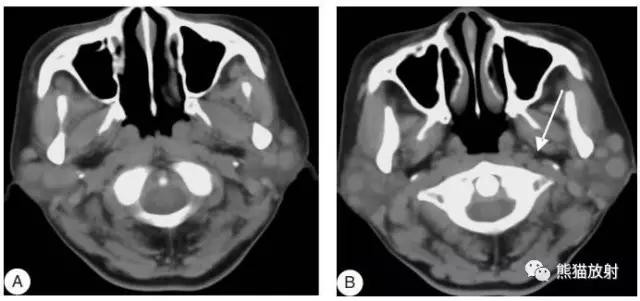

女性,45岁,淋巴瘤。显示双侧腮腺区、左侧咽后区淋巴结增大,病变无融合倾向。

女性,56岁,箭头显示右侧颈部ⅡA区转移性低分化癌。